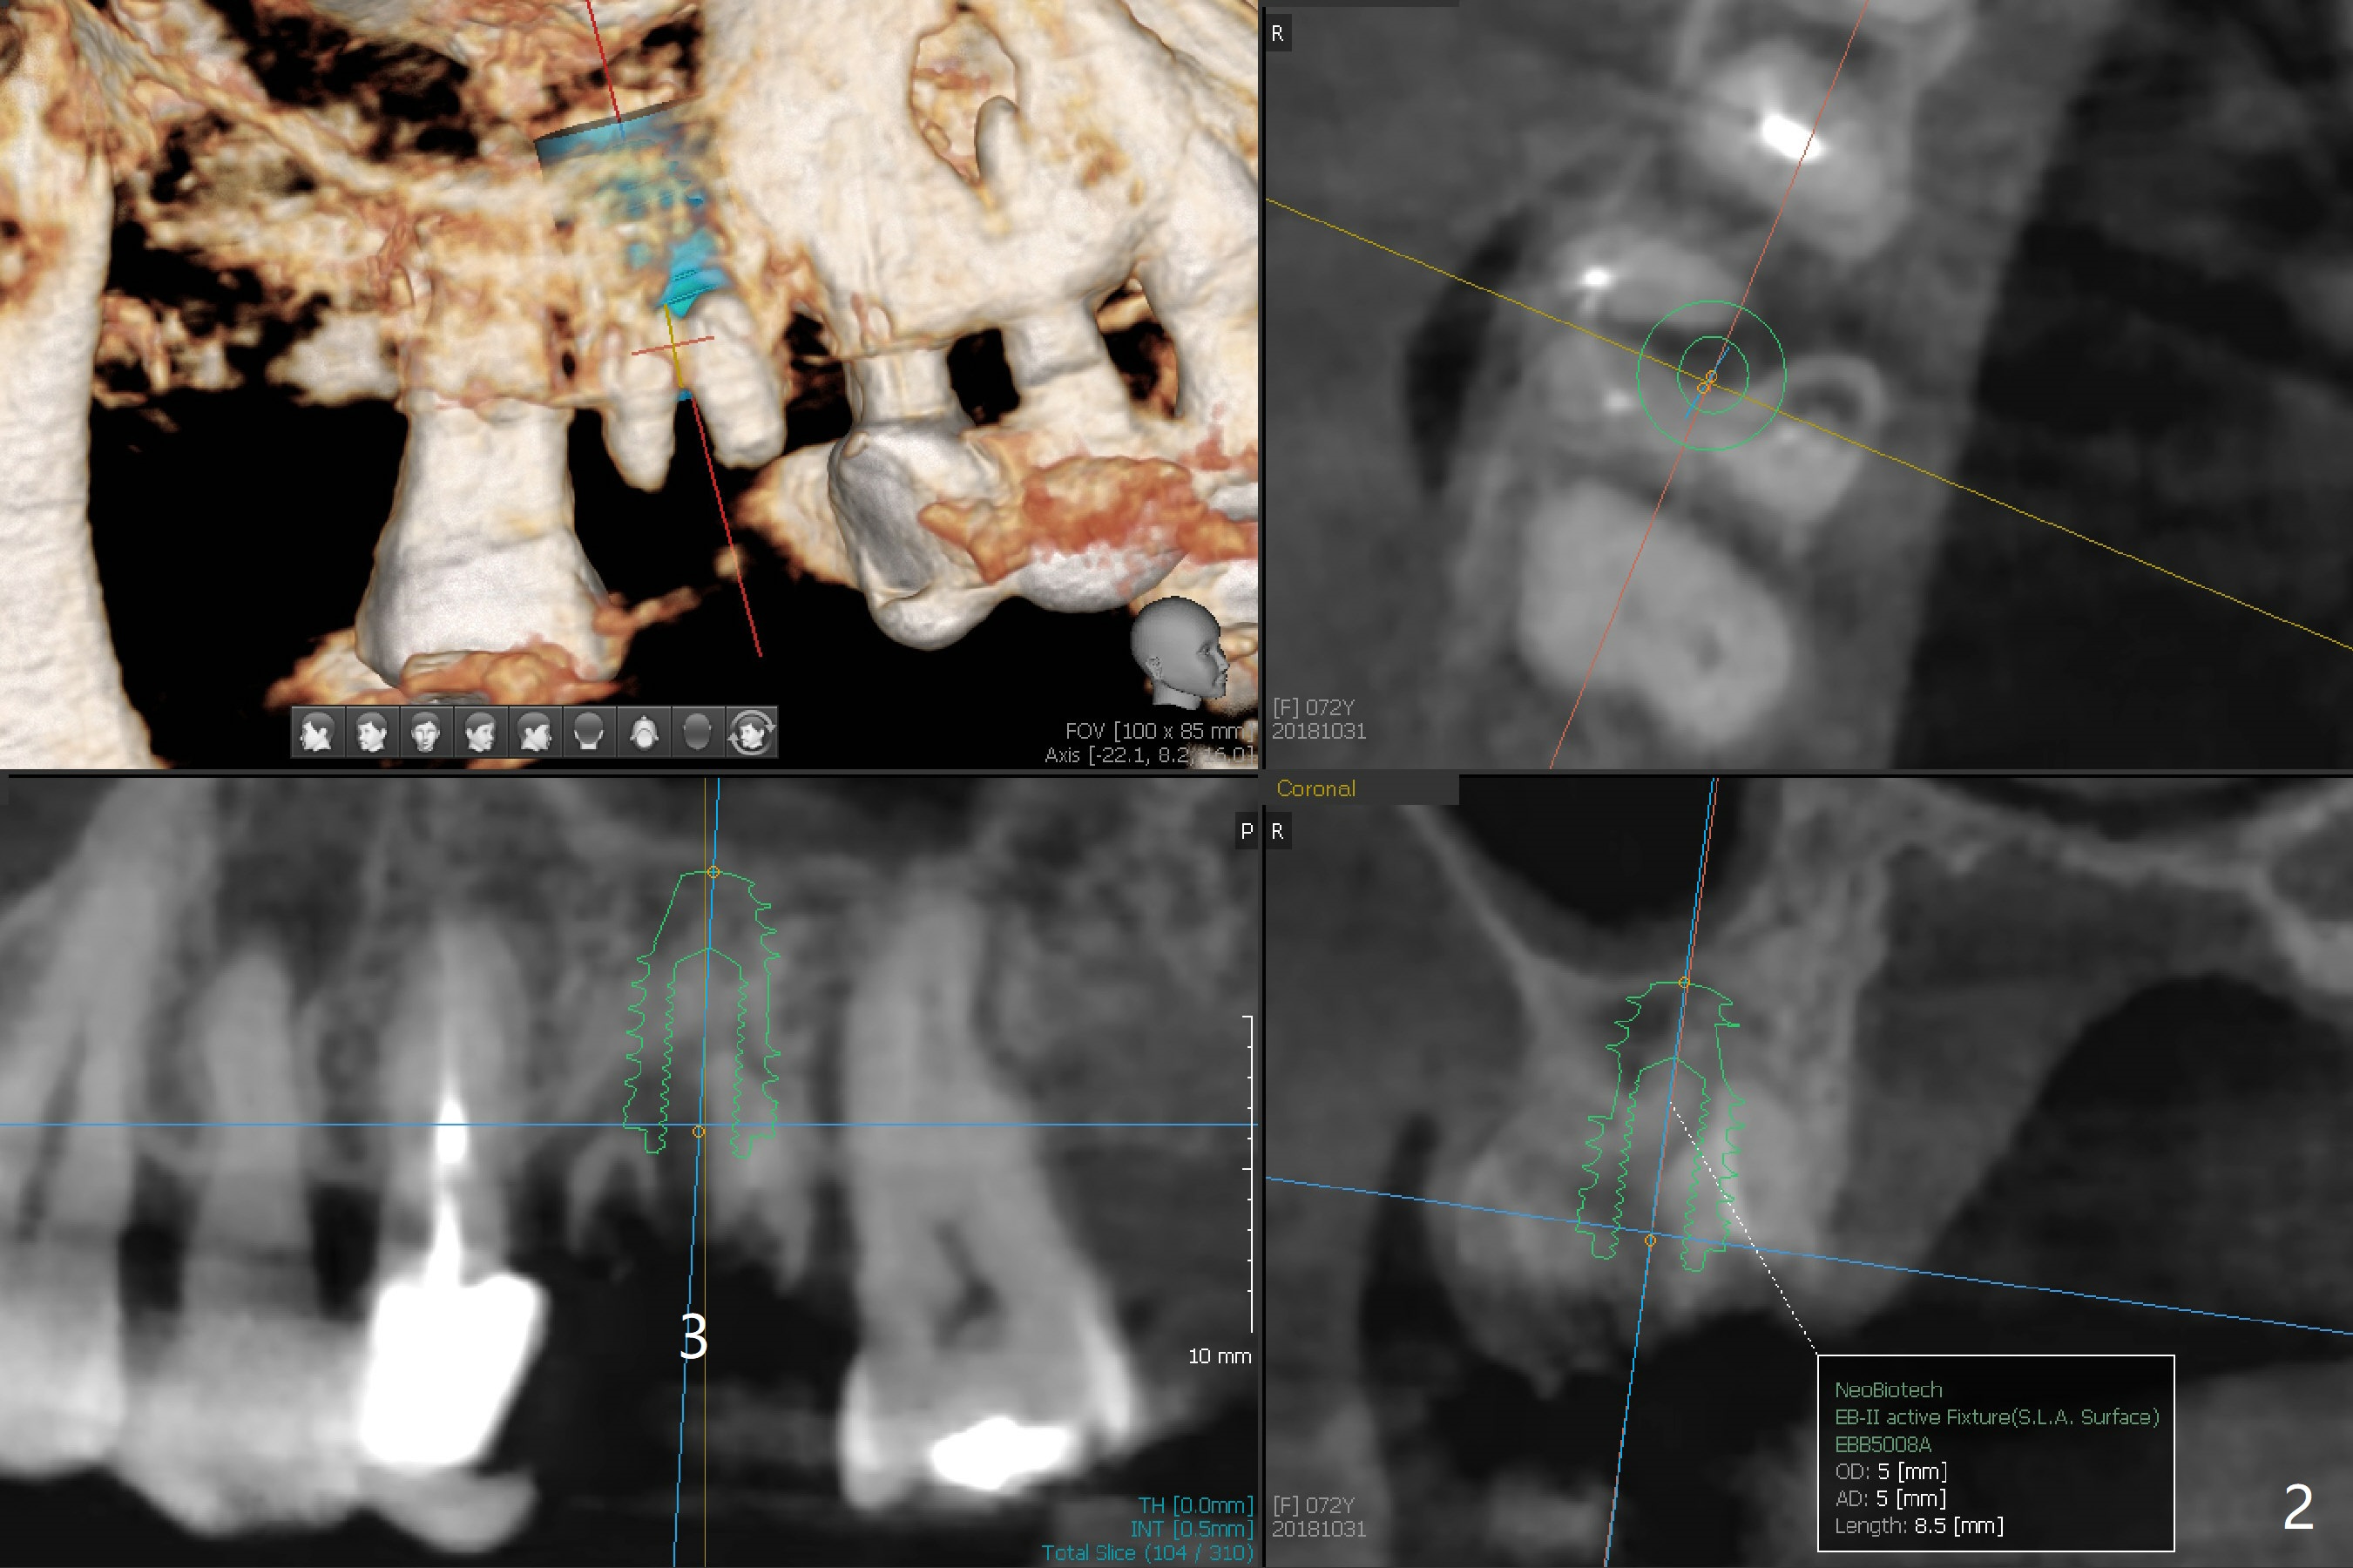

A 72-year-old woman returns with loss of crown at #3 one and 2 years post cementation at #26 and #11-15 (Fig.1). It appears that immediate implant achieves better trajectory with guide than without it when osteotomy involves the septal bone in a molar (Fig.2). Take photos after extraction, after initial osteotomy, and after implantation to show that the osteotomy stays in the middle of the socket in spite of the sloped septum.